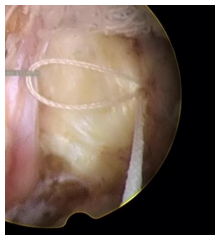

脊柱修復(fù)與重建技術(shù)之纖維環(huán)縫合術(shù)是在各種針對椎間盤突出癥的手術(shù)術(shù)式輔助下,閉合纖維環(huán)上殘留的破口,技術(shù)特點如下:

1、纖維環(huán)縫合手術(shù)是對椎間盤形態(tài)進行的修復(fù),促進了纖維環(huán)破口的愈合,是對以纖維環(huán)破裂所造成的椎間盤突出癥直接和有效的治療手段。

2、即刻閉合纖維環(huán)的破口,顯著降低椎間盤內(nèi)殘留髓核受力后從纖維環(huán)破口處再突出的復(fù)發(fā)幾率。

適用于椎間孔鏡、椎間盤鏡、雙通道脊柱微創(chuàng)手術(shù)技術(shù)(UBE),顯微鏡、通道管等微創(chuàng)手術(shù)髓核摘除后纖維環(huán)的修復(fù),降低術(shù)后復(fù)發(fā)率